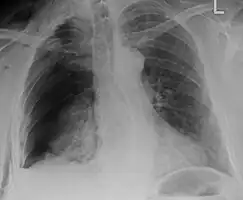

An X ray showing multiple old fractured ribs of the person's left side as marked by the oval.

Plain X-rays often pick up displaced fractures but often miss undisplaced fractures.[13] CT scanning is generally able to pick up both types of fractures.[13]